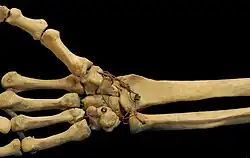

Las articulaciones carpometacarpianas (CMC) son cinco articulaciones de la muñeca que articulan la fila distal de los huesos del carpo y las bases proximales de los cinco huesos metacarpianos.

Dedos

- El segundo metacarpiano se articula principalmente con el trapezoide y secundariamente con el trapecio y el capitado.

- El tercer metacarpiano se articula principalmente con el capitado,

- El cuarto metacarpiano se articula con el capitado y el hueso ganchoso.

- El quinto metacarpiano se articula con el hueso ganchoso.[7]

Entre ellos, los cuatro metacarpianos cubitales también se articulan con sus vecinos en las articulaciones intermetacarpianas.[7]